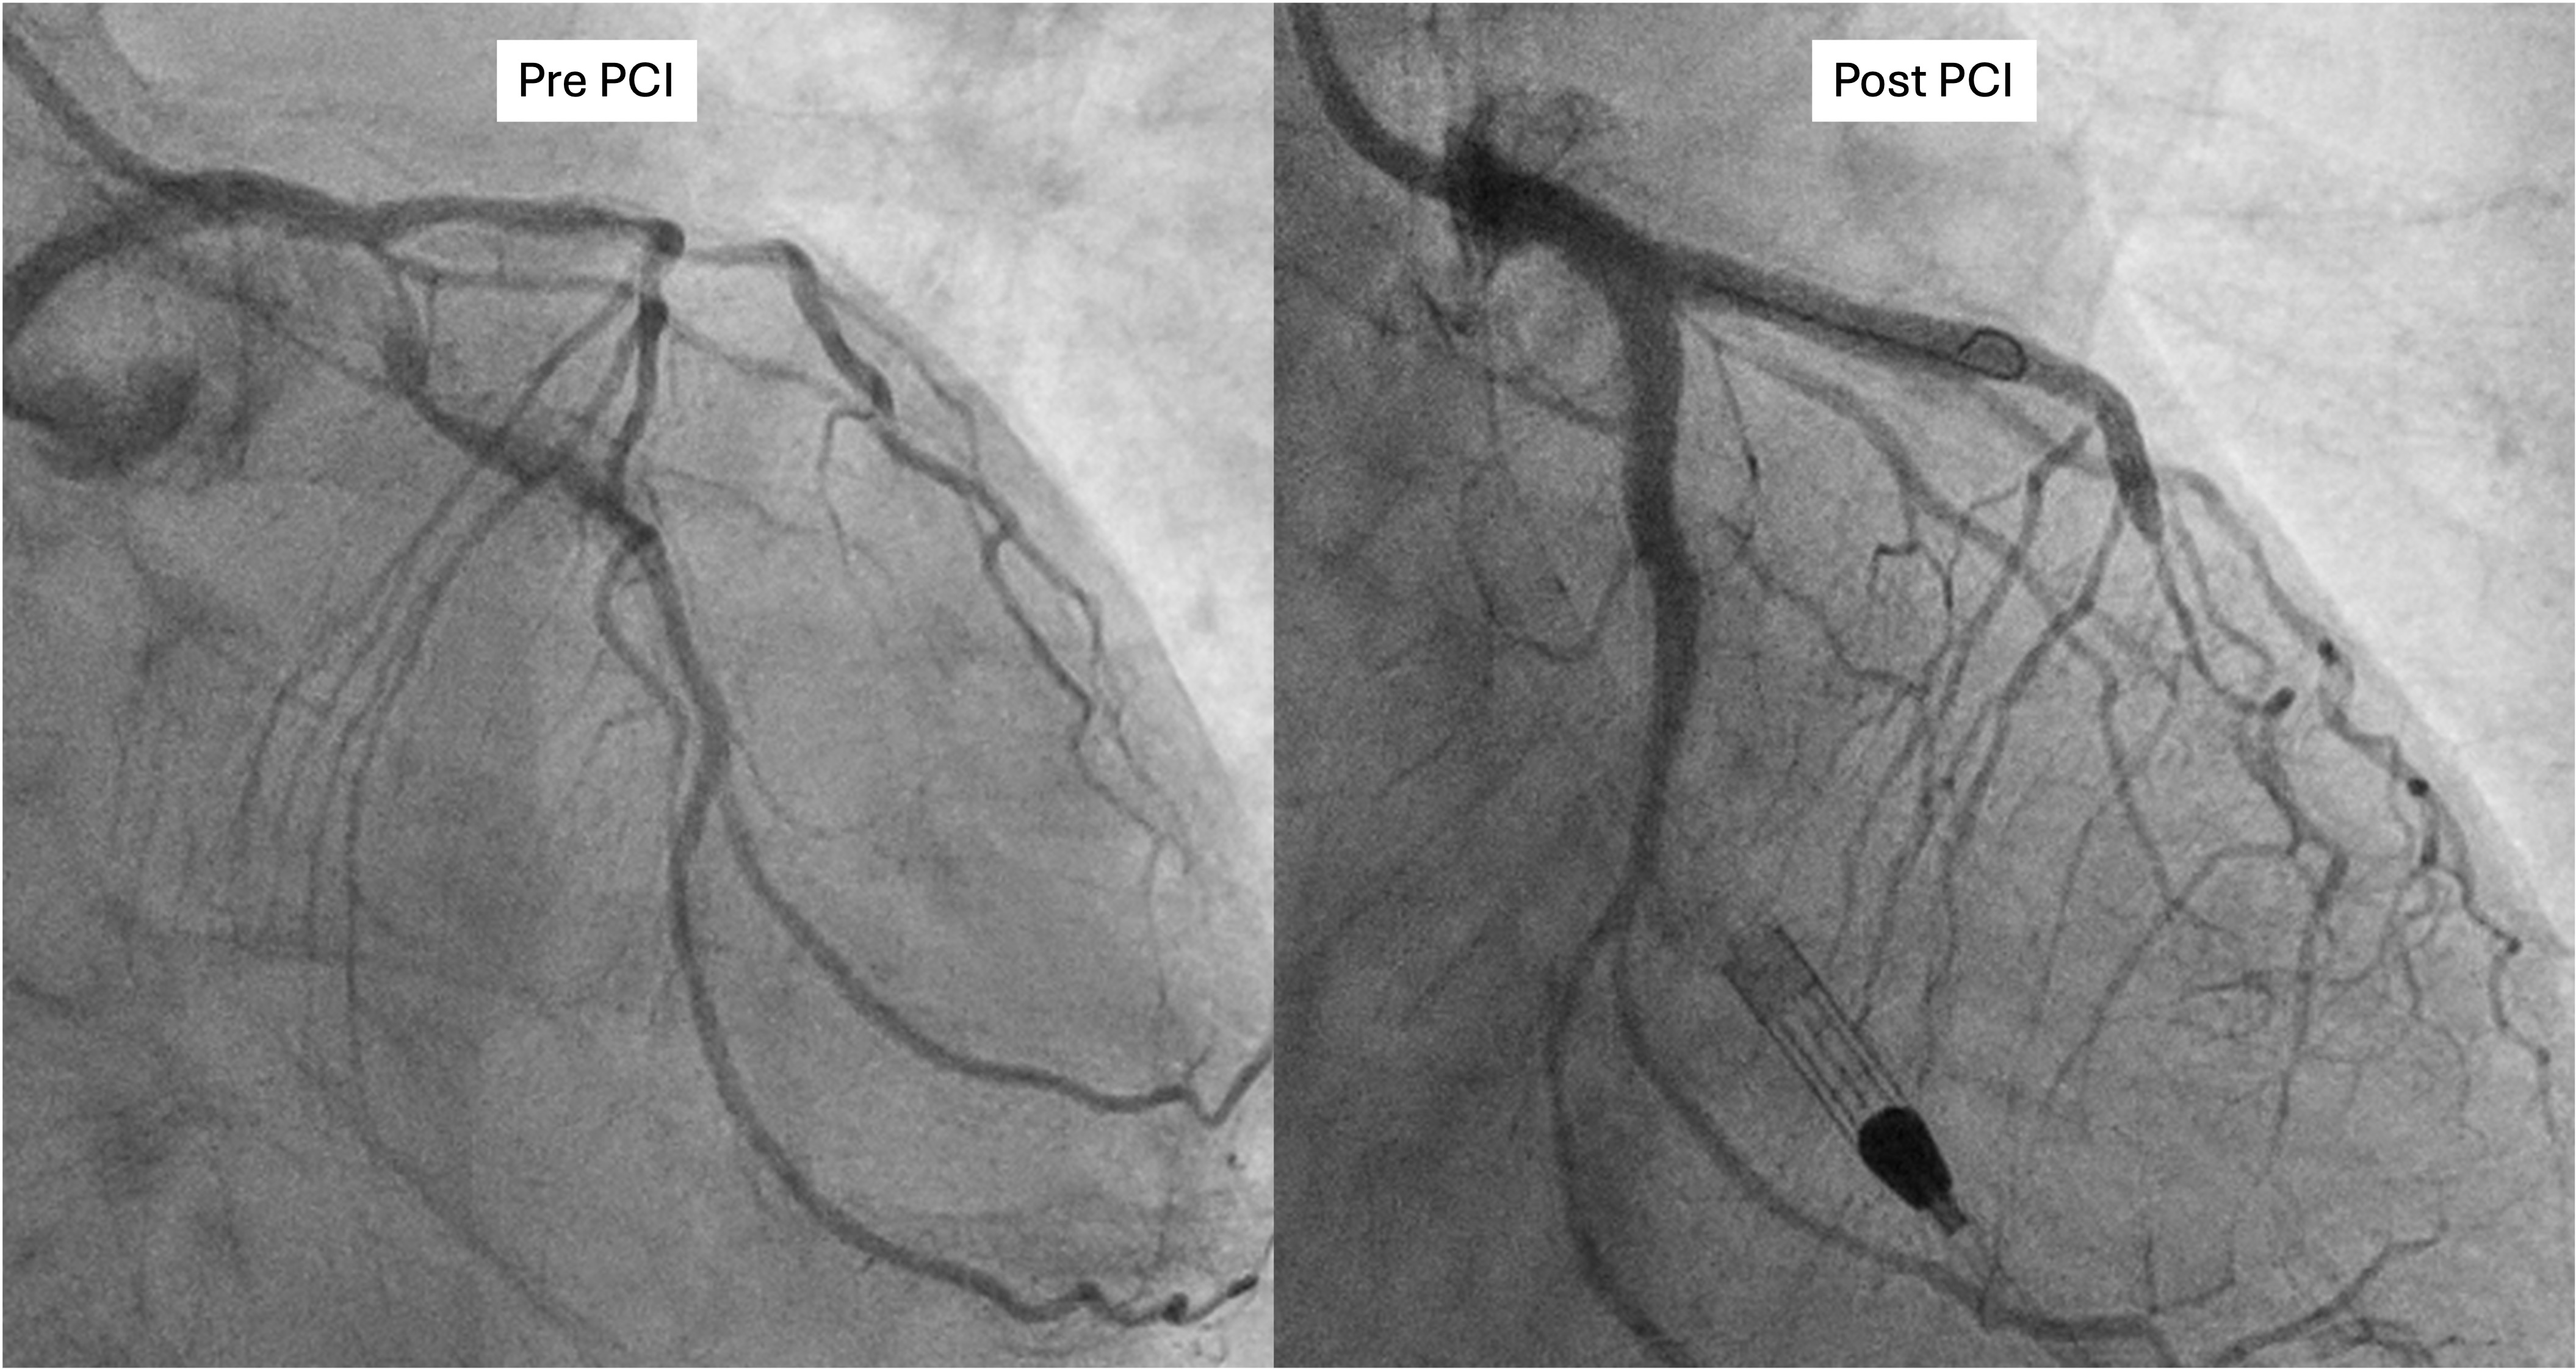

The Vascular team performed aortoiliac revascularisation to concurrently treat his peripheral vascular disease and allow for femoral access for CHIP. Kissing covered stents were placed from the abdominal aorta to bilateral CIAs and EIAs using the ¡°pave and crack¡± technique with chimney stenting to the IMA. After recovery, single access for Impella CP supported high-risk PCI (SHiP) was performed via the left femoral artery with a 7F sheath through the 14F Impella sheath. Intervention began with the LAD using rotational atherectomy (1.25mm burr) but led to hemodynamic instability despite Impella support, requiring emergency intubation and dopamine infusion. Significant blood loss was noted from the SHiP access due to the inadvertent migration of the PCI sheath proximally, and addressed by repositioning the sheath and transfusion. Once stabilised, the LAD, diagonal, and LCx arteries were treated with rotational atherectomy (1.25mm burr). The LCx had follow up orbital atherectomy, and scoring balloon angioplasty for a large ostial calcific nodule. The left main stem bifurcation was treated with drug eluting stents using OCT guided nano crush technique (3.5/28mm LMS-LAD, 3.5/28mm LCx). The first diagonal and mid LCx were treated with drug eluting balloons (2.5/30mm, 2.5/20mm). Final POT was performed in the LMS (4.0/8mm non-compliant at 18atm). Final OCT and angiography showed satisfactory result with TIMI 3 flow.